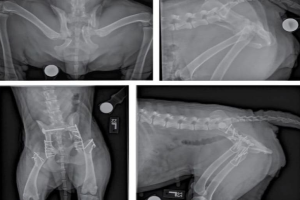

7.2. Phẫu thuật xương khớp

Sửa chữa gãy xương, trật khớp, phục hồi khả năng vận động.

Phẫu thuật xương khớp cho thú cưng tại Sing Pet Biên Hòa, Đồng Nai. Bác sĩ giỏi, trang thiết bị hiện đại, chăm sóc hậu phẫu tận tâm, giúp thú cưng hồi phục nhanh và an toàn.